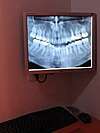

La radio panoramique est un examen de dépistage de problèmes indétectables à l'examen clinique.

Cette toute dernière génération d'appareil de radiologie dont vient de se pourvoir notre cabinet permet de diagnostiquer certains problèmes invisibles lors d'un simple examen clinique mais aussi de conrôler la qualité ou l'efficacité des traitements mis en oeuvre.

Cette radio étendue aux deux arcades dentaires apporte d'avantage de renseignements qu'un cliché rétro-alvéolaire "classique" se limitant à une ou deux dents.

Elle permet de visualiser l'ensemble des deux arcades dentaires et les tissus adjacents.

En donnant des notions précises sur la densité des tissus traversés, les radios panoramiques permettent de déceler des problèmes, d'observer les configurations anatomiques internes ou de mesurer la qualité des oins profonds, insoupçonnables lors d'un simple examen clinique. L'étendue des services rendus par ce type de cliché est presque sans limite et établir la liste de ces services serait une entreprise de longue haleine. Nous pouvons citer néanmoins la visualisation de reprise de carie sous une obturation, la proximité d'un fond de carie par rapport au nerf de la dent, l'intensité d'un déchaussement, la position des dents de sagesse incluses, l'absence éventuelle de germes dentaires, la taille des sinus, la qualité de l'os , etc.....